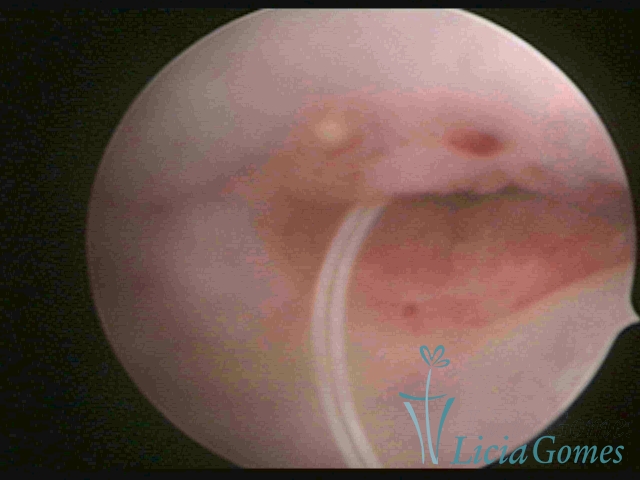

Cavidade uterina com DIU